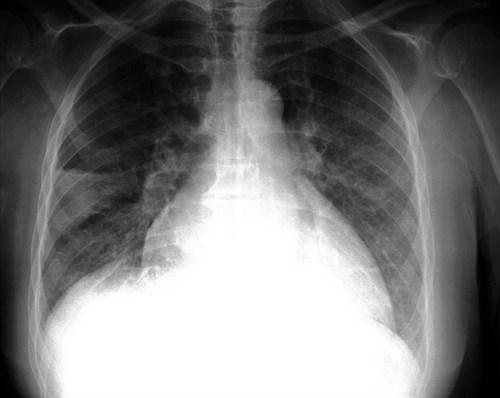

La fibrosis pulmonar puede desarrollarse después de lesiones pulmonares, como infecciones, radiación o quimioterapia, o puede tener una causa desconocida, como en la fibrosis pulmonar idiopática (FPI). La FPI es un trastorno pulmonar progresivo y finalmente fatal que afecta a más de 150.000 pacientes al año en Estados Unidos y más de 5 millones en todo el mundo.